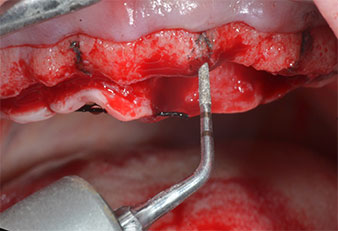

Insert Piezomed I2A/I2P

Fig. 4 : L’étape suivante est l'agrandissement pilote à l'aide des inserts Piezomed I2A/I2P, qui sont utilisés selon un mouvement horizontal rotatif.